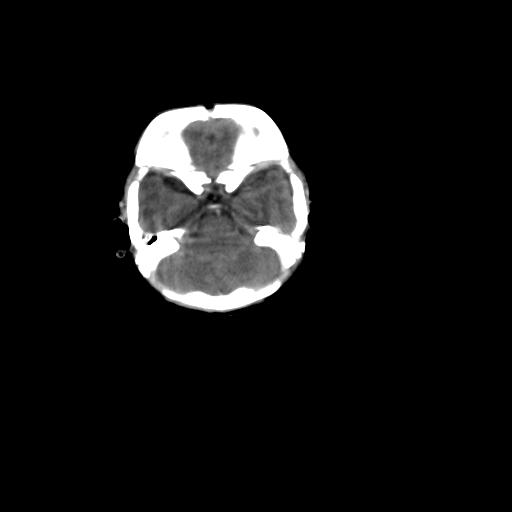

男,12天,自然分娩,其母发现右顶部头皮包块逐渐增大。

右顶部头皮血肿

右顶部头颅血肿(骨膜下血肿)

右顶骨呈膨胀性改变,骨纤维结构不良?

右顶部头皮血肿。

右顶部头皮血肿,可能是产道挤压所致。以后会慢慢恢复。

鉴别:骨膜下血肿,一般为产伤,应用产钳之类的吧

疑问:患儿脑白质密度比较低,基底节区密度比较高,类似于“双圈征”脑沟密度也偏高。该婴儿可有别的异常吗?反射正常吗?评分能达到5分吗?如果正常,就随诊观察吧。不正常要考虑到缺血缺氧性脑病。